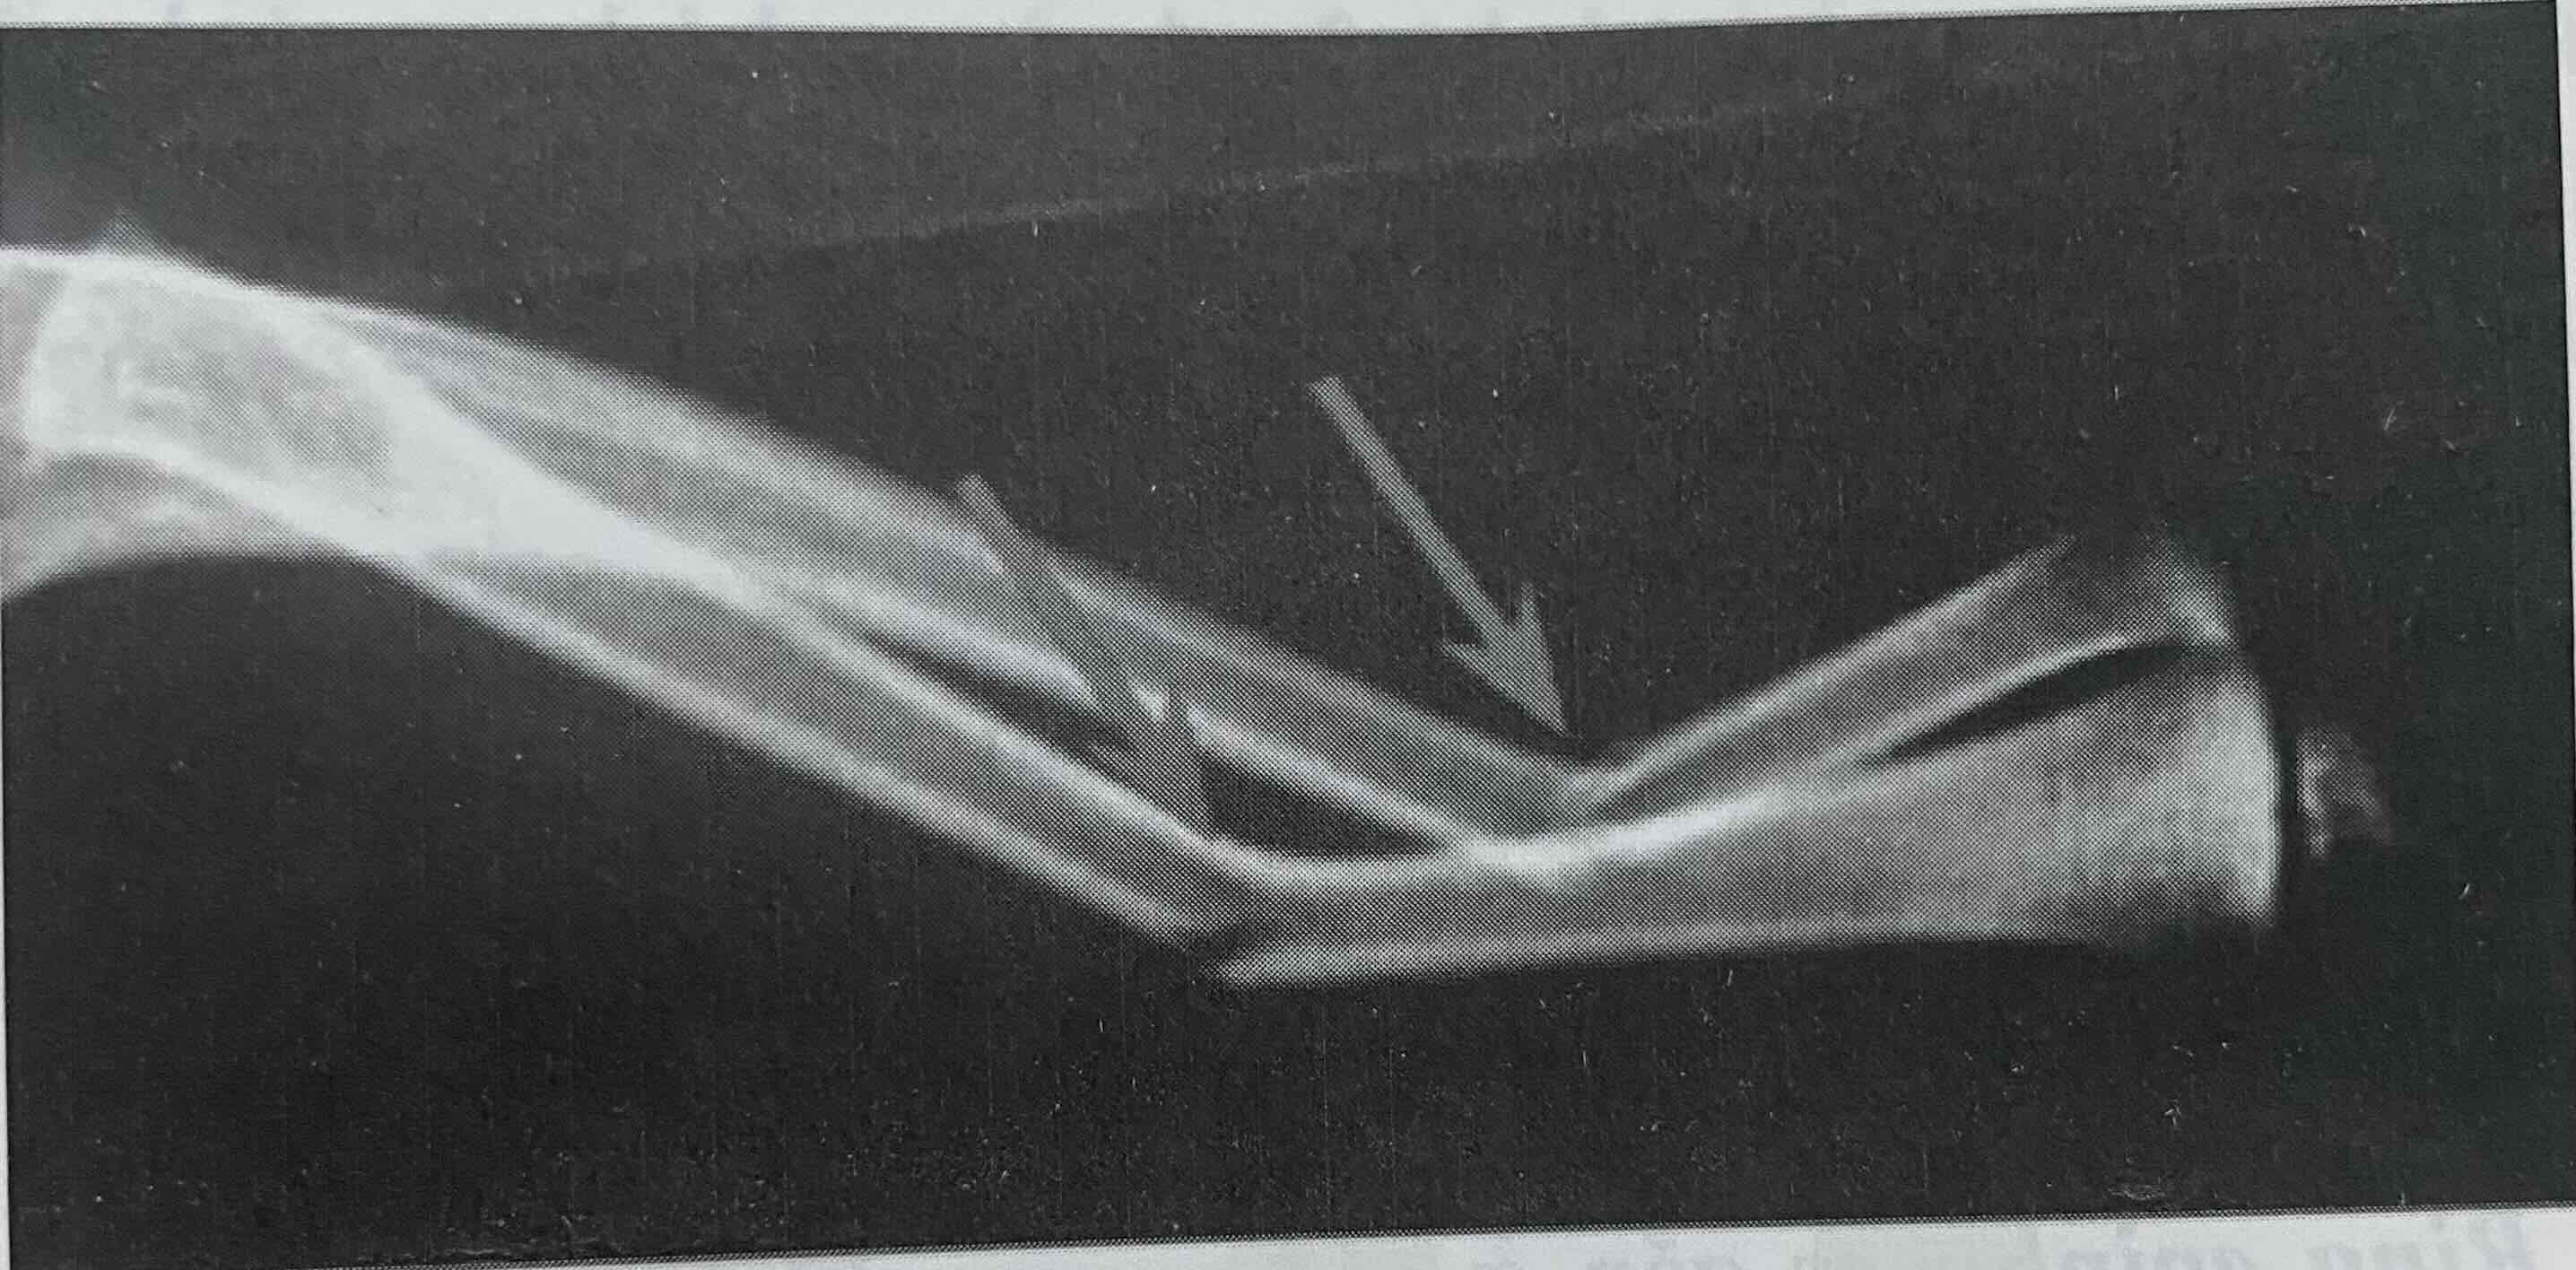

Hình: Gãy cong tạo hình xương trụ, trật khớp quay trụ trên, thường gặp ở trẻ em (Nguồn: LynnT. Stahely, Practice of Pediatric Orthopaedic, 2008)

Màng ngoài xương trẻ em dày và chắc giúp tạo ra những kiểu gãy riêng chỉ có ở trẻ em.

Gãy với màng ngoài xương nguyên vẹn có thể khiến xương ít lệch và khó nhận ra (gãy cong tạo hình).